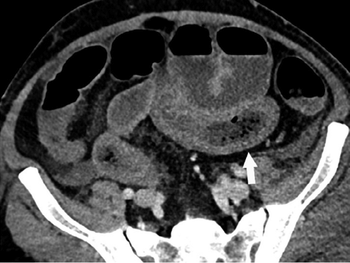

Amazon Alexa skill RAD-Assistant successfully retrieves pulmonary nodule and ovarian cyst clinical follow-up guidelines.

A five-tiered approach to cross-sectional interventional procedures can help radiologists determine which patients to treat first, minimizing likelihood of viral transmission.